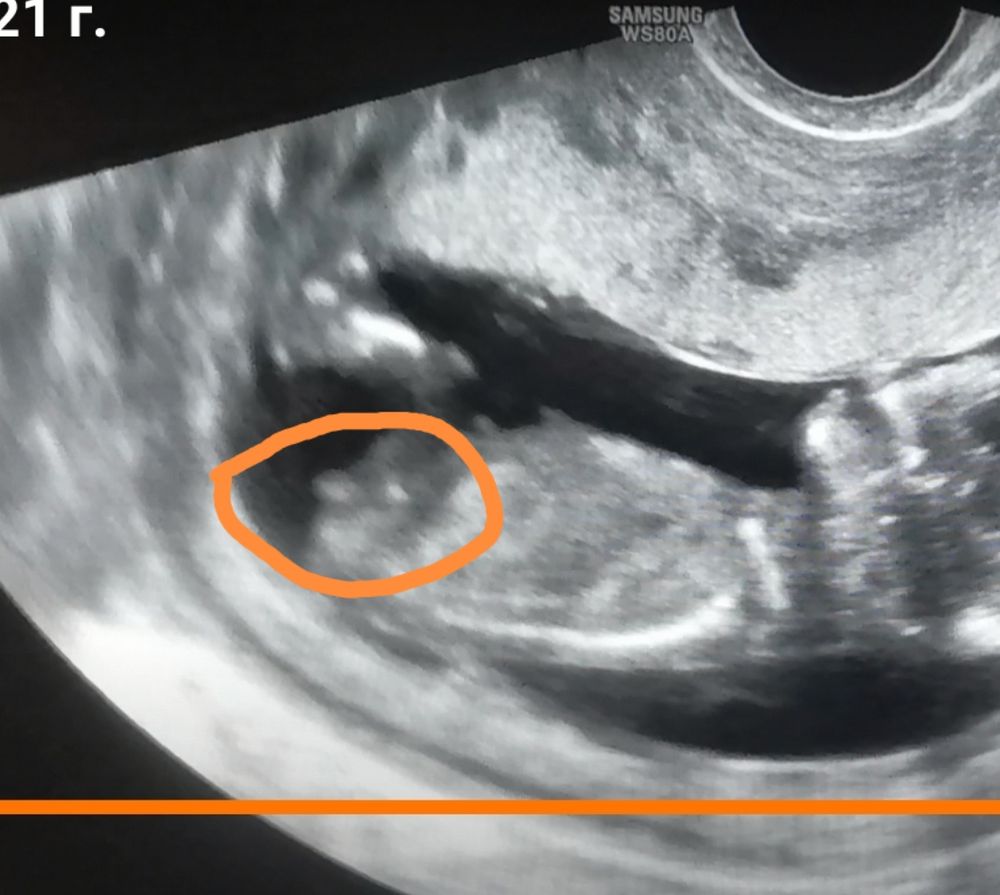

Дарья, мне на узи сказали пол, потом кстати сама с видео и рассмотрела бугорок! Убедилась так сказать, вот скрин. Может и вы рассмотрите! Повнимательнее

18.08.2021